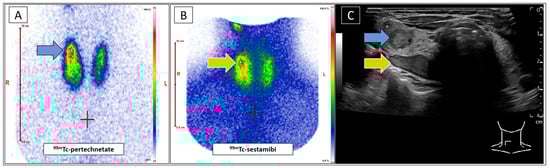

Simultaneous Identification of Tc-99m-Sestamibi-Positive Autonomous Thyroid Adenoma and Adjacent F-18-Ethylcholine-Positive Parathyroid Adenoma in Patient with Graves’ Disease Using Real-Time Ultrasound Fusion Imaging

Leder, T.; Seifert, P.; Gühne, F.; Freesmeyer, M. Simultaneous Identification of Tc-99m-Sestamibi-Positive Autonomous Thyroid Adenoma and Adjacent F-18-Ethylcholine-Positive Parathyroid Adenoma in Patient with Graves’ Disease Using Real-Time Ultrasound Fusion Imaging. Diagnostics 2025, 15, 1262. https://doi.org/10.3390/diagnostics15101262